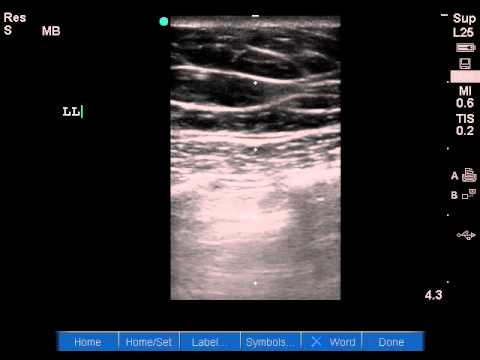

Each site was scanned twice at each time point. Identification of a lung point on lung us yields 100% specificity for pneumothorax (58). A pneumothorax can be caused by: Place a linear (vascular/soft tissue) probe in the most anterior point of the chest wall, usually at about the 3rd or 4th intercostal space. The presence of a 'lung point' indicates pneumothorax. These are the thoracic radiographs: Ultrasound scans in all 43 examinable patients with pneumothorax showed absent lung sliding, 41 of 43 patients had the a line sign, and 34 exhibited a lung point. A recent review article by wilcox in jama questions whether ultrasound guidance truly reduces the risk of pneumothorax.

A pneumothorax separates the visceral and parietal pleura, eliminating normal lung sliding between these layers on lung us. Once you understand these basic lung ultrasound findings you will be able to interpret just about any lung ultrasound images. When m mode is used on a normal lung, the lung (and the air inside it) moves back and forth across this single ultrasound beam creating a picture that is often compared to a sandy beach. Unless the pneumothorax is loculated or there are adhesions, the gas moves freely within the thoracic cavity. There is normal lung sliding on the right side. Lung ultrasound pathology profiles such as pneumothorax, pneumonia, cardiogenic pulmonary edema, etc will have a different combination and distribution of these pathological lung ultrasound findings/signs. Nov 08, 2017 · primary spontaneous pneumothorax: 3 article feature images from this case Ein pneumothorax (gelber pfeil) mit noch geringer. To evaluate for pneumothorax with ultrasound, have the patient lay supine. In the supine trauma patient, this will typically be the anterior chest wall lateral to the sternum in the second intercostal space. Among 302 analyzable controls, 65 had absent lung sliding, 16 of them showed an a line sign, and none showed a lung point. Each site was scanned twice at each time point.

Ruling out a pneumothorax is the easy part for me, and it doesn't require much more than a quick visual inspection. Ultrasound can also allow semiquantitative assessment of pneumothorax size by assessing the position of the lung point. Once you understand these basic lung ultrasound findings you will be able to interpret just about any lung ultrasound images. · february 14, 2020 · 1 min read. Nov 08, 2017 · primary spontaneous pneumothorax: Ultrasound use may therefore obviate the need for ct in a majority of cases. Additionally, it can result in timely diagnoses specifically in neonatal pneumothorax. The probe should be oriented perpendicular to the ribs (usually marker dot towards the head). You can also use m mode, or motion mode, which provides an image showing tissue motion along a single ultrasound beam. Unless the pneumothorax is loculated or there are adhesions, the gas moves freely within the thoracic cavity. At its heart, the concept behind using ultrasound to evaluate for air in the space between the visceral and parietal pleura is straightforward. Ultrasound scans in all 43 examinable patients with pneumothorax showed absent lung sliding, 41 of 43 patients had the a line sign, and 34 exhibited a lung point. Ultrasound outperforms cxr in evaluation of pneumothorax in blunt trauma patients, but there cite this article as: